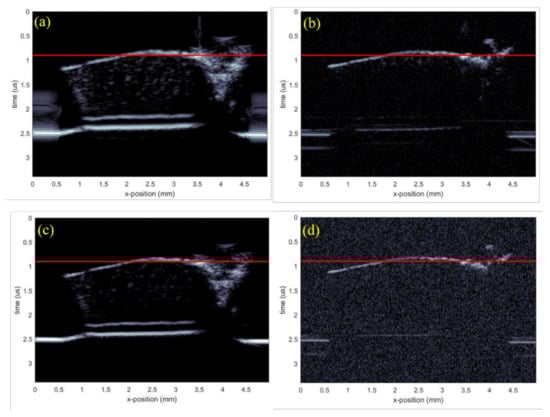

The corresponding results when using a chirp excitation pulse are shown in Figure 7c,d. B-scans of the test sample are shown in Figure 8a,d, with the figures corresponding to the transducer-waveform combinations previously used in Figure 4. The red lines in Figure 8 show the spatial locations where the C-scans in Figure 7 were taken. This shows that the backscattered signals were generated from the internal structures, i.e., arising from the cells of cartilage. From Figure 7 and Figure 8, we observe by comparison, that the commercial transducer yielded a significantly higher SNR than the in-house transducer. Single-pixel (salt and pepper) noise is, for example, clearly visible in all domains of Figure 7b, while it cannot be spotted in Figure 7a. The observed difference in SNR is probably strongly related to the difference in transducer aperture sizes listed in Table 1. The signal-to-noise ratio was calculated from the ratio of the average value of the signal to the standard deviation of the signal. The SNR was calculated for all the cases and the results are shown below in Table 2.

The commercial transducer also explored more details from the inner parts of the cartilage, especially from the deepest parts [36]. This is clearly seen, e.g., by comparing the results for the chirp waves shown in Figure 7c,d. Here, Figure 7c shows elliptical-shaped scatters originating from cells through the entire sample, while these scatters were visible only towards the upper surface in Figure 7d.

On the other hand, the elliptical scatters from the in-house transducer appeared significantly smaller than from the commercial transducer, suggesting that the point-spread function from the latter was larger. However, the penetration depth remained the same because both the transducers were operating at the same frequency, evident from the B-scan in Figure 8. This came from the complex inverse relationship between spatial resolution and penetration depth. It was also possible to observe finer details on the C-scan from the in-house transducer, which, together with a smaller point-spread function, suggest that this transducer had a significantly better resolution. This result can to some extent be explained by the smaller f-number of the in-house transducer.

Figure 8. B-scan images generated of the test sample using different transducers and excitation pulses. (a) Commercial transducer with Ricker wavelet, (b) in-house transducer with Ricker wavelet, (c) commercial transducer with chirp code, and (d) in-house transducer with chirp code.